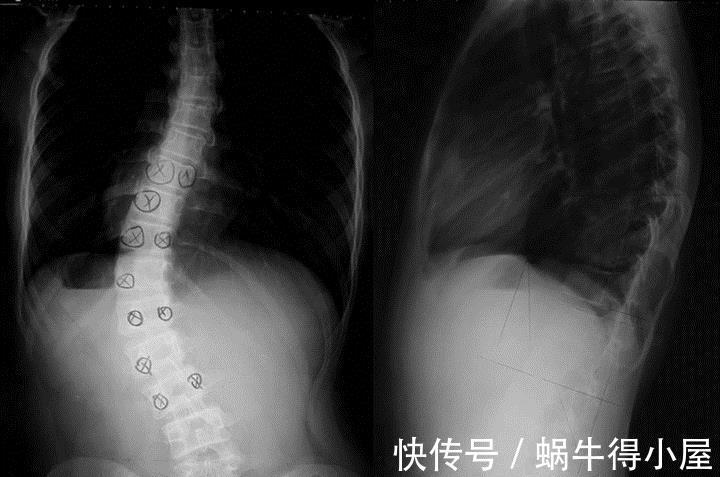

如何排查孩子是否是脊柱侧弯?

其实在家可以简单自测。

首先,在人直立的时候,可以从稍远的地方,目测两个肩膀是否在一个水平线上。

其次,也可以让孩子背对我们,用手按着他们的肩胛骨的底部看是否水平。

最后,再分享一个动态的方法给大家,这个时候可以让孩子弯腰90度,自然我们就可以看出脊柱是否有凸起不对称的地方了。